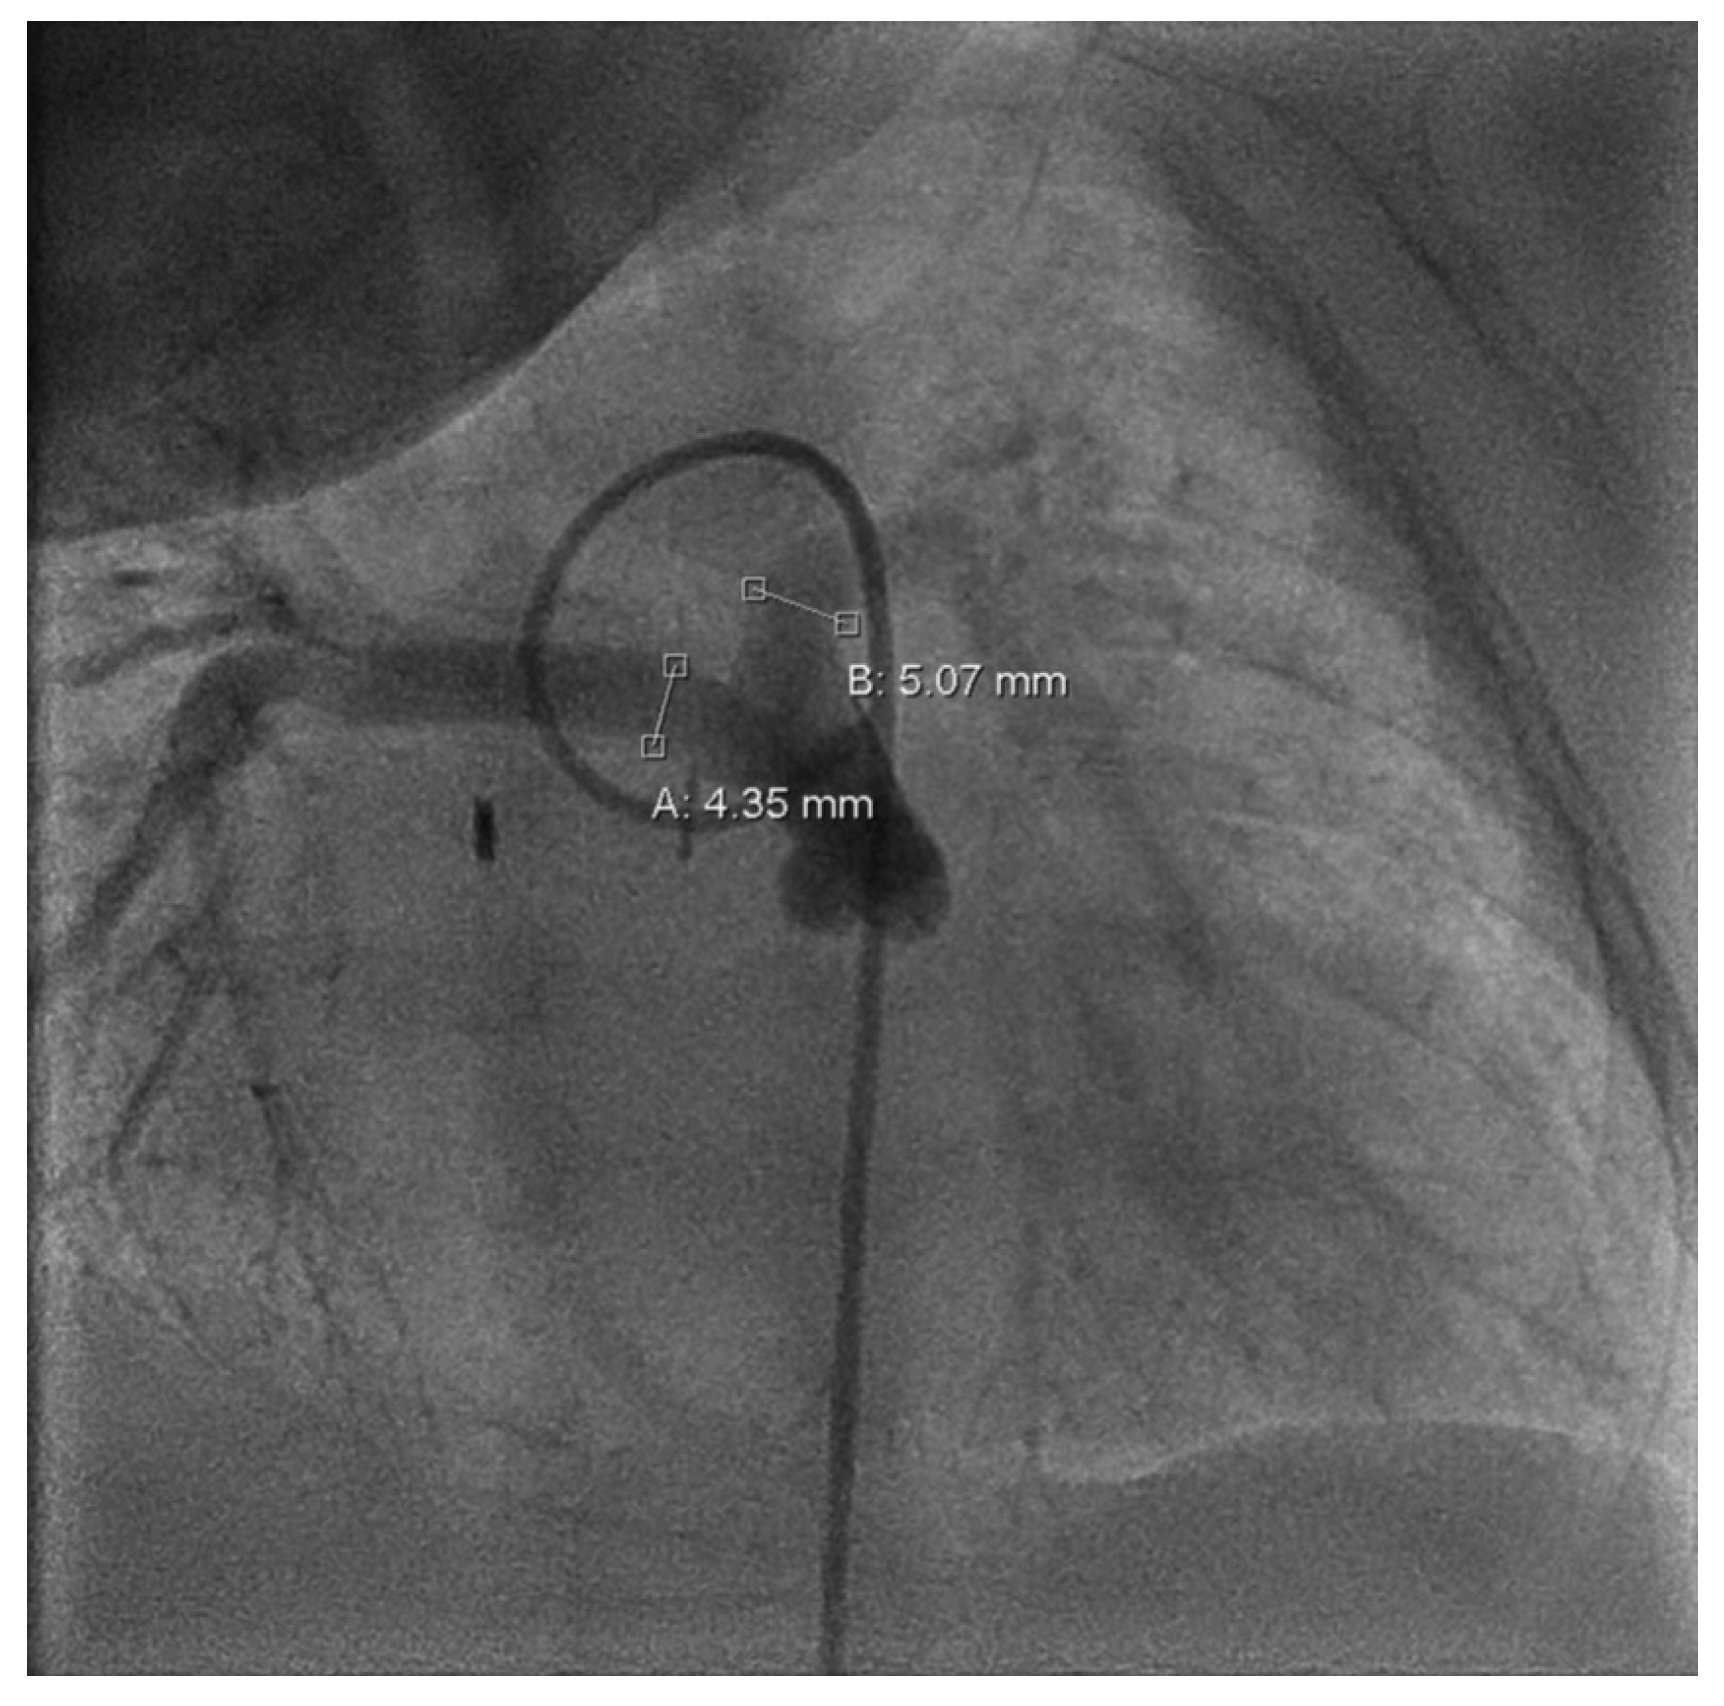

Figure 3. Cardiac catheterization, a.p.; measurement of the left pulmonary artery (=B: 5.07 mm) and right pulmonary artery (=A: 4.35 mm) diameter.

Follow-up in the third month of life confirmed preserved LV function (FS = 38%) and bidirectional shunt flow across the Starnes patch with an estimated RV pressure of 10 mmHg and a well-perfused AP shunt with a stable gradient of 4 m/s. Both hypoplastic PAs were perfused (LPA > RPA; LPA = 4.9 mm, RPA = 2.3 mm). Due to increasing LPA/RPA imbalance and filiform, laminar RPA flow, sectional imaging was performed via magnetic resonance imaging (MRI). Because of the bilaterally small-caliber PAs without dilatable local stenosis and insufficient RV volume for biventricular correction, we opted for interventional dilation of the AP shunt clip. As part of the corresponding cardiac catheterization (CC) at the beginning of the fourth month of life, several balloon dilatations of the AP shunt in clip position to a maximum of 4 mm were performed. The PAs appeared to be more prominent on CC than depicted in MRI (LPA = 5 mm, z = −0.2; RPA = 4.3 mm, z = −1.1; see Figure 3).